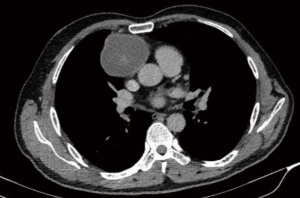

Early studies with VATS thymectomies for myasthenia gravis (MG) in children has established its ability to achieve a complete resection and benefit similar to adult series (36,37). DeCou et al. reported resection in 5 children with neuroblastomas via thoracoscopy and achieved a complete resection with good short term survival (38). However, they had tumor spillage in a couple of cases. All tumors were stage 1 and ≤6 cm size. So the feasibility of VATS in well encapsulated tumors (Figure 1) is well established but those with large tumors with higher stages remains a concern.